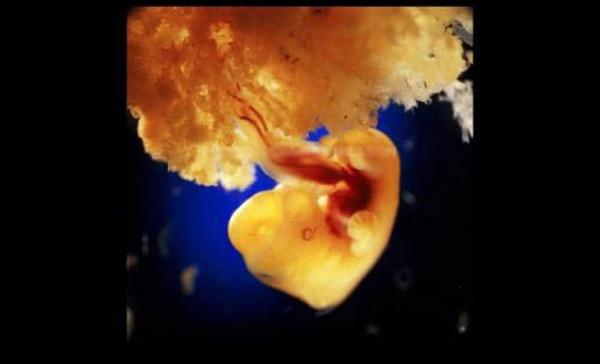

40 ημερών. Τα εξωτερικά κύτταρα του εμβρύου ενώνονται με την χαλαρή επιφάνεια του τοιχώματος της μήτρας για να σχηματίσουν τον πλακούντα